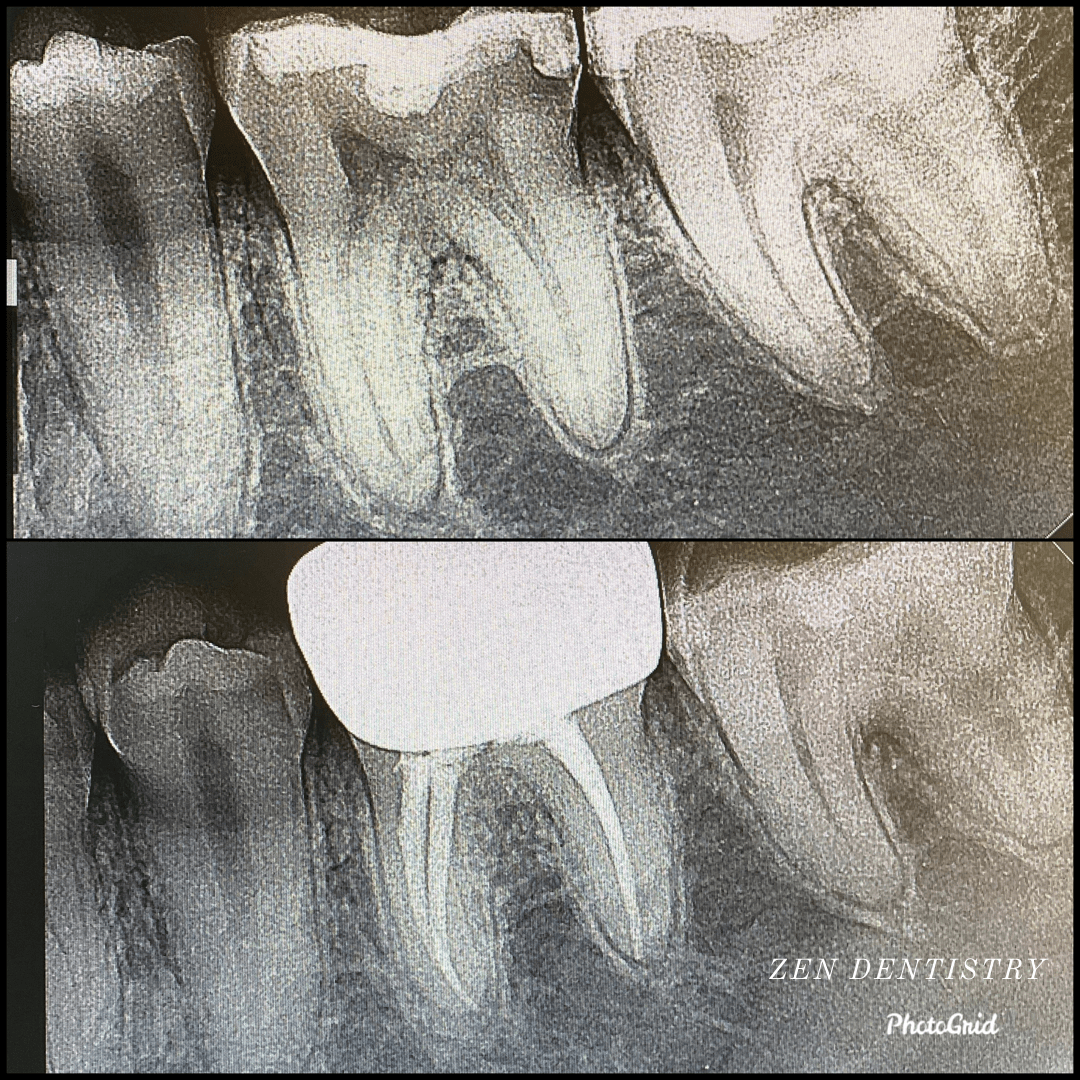

Patient presented to the A thorough clinical exam, endodontic screening and proper x rays led to the diagnosis of irreversible pulpitis(inflamed pulp tissue) due to secondary dental caries with inflamed periodontal ligaments.